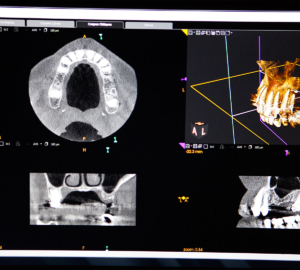

1. Consultation initial

Lors de la première consultation, une analyse précise de votre situation bucco-dentaire est réalisée. Des radiographies panoramiques et 3D, ainsi que des empreintes numériques, permettent d’établir un plan de traitement personnalisé.